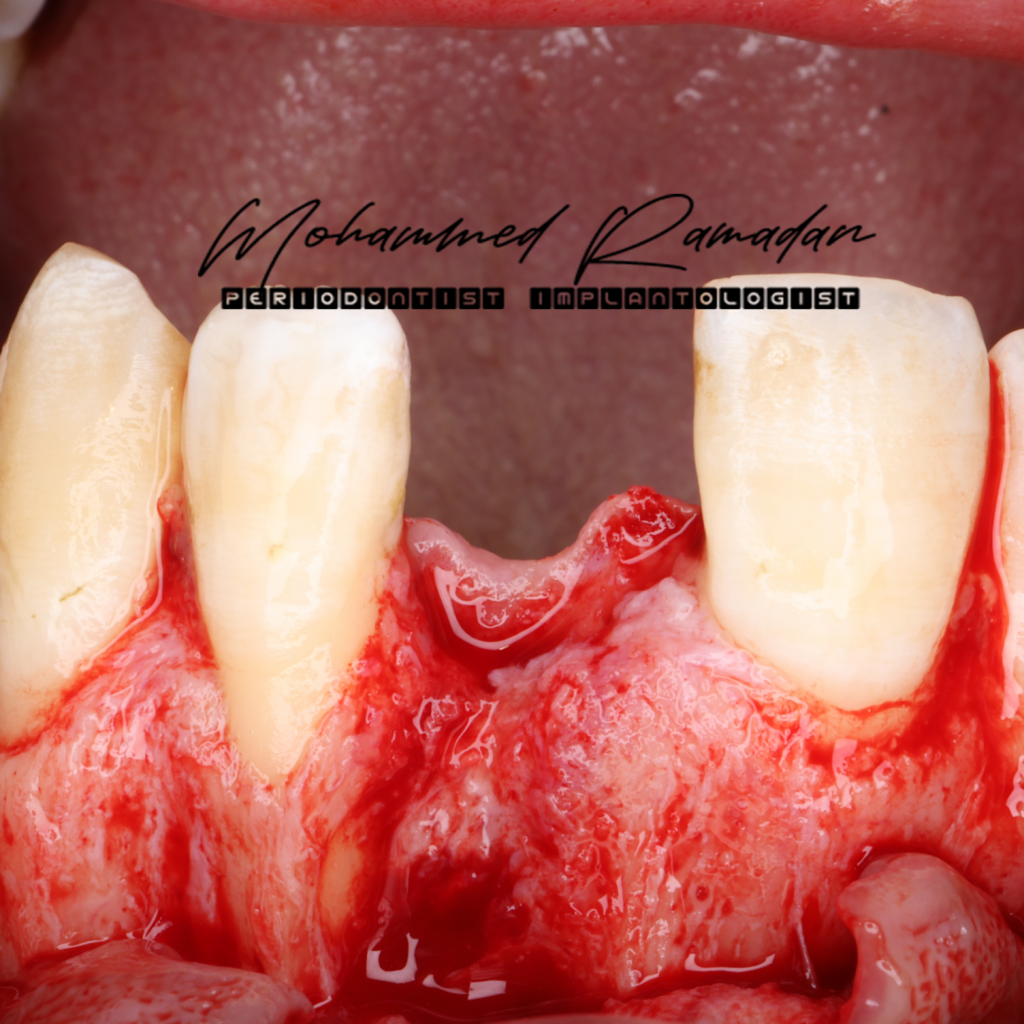

Stage One: Implant Placement and GBR

- A full-thickness mucoperiosteal flap was elevated.

- Guided osteotomy preparation was performed, followed by fully guided implant insertion.

- Intraoperative Challenge: The implant was exposed from platform to apex. Despite this, adequate primary stability was achieved via palatal bone engagement.

- Possible Cause of Discrepancy: Poor CBCT quality with wide grayscale range, potentially misinterpreted as bone.

- Decision-Making: Although a staged approach was considered, patient time constraints necessitated continuation with simultaneous GBR using the sandwich technique.